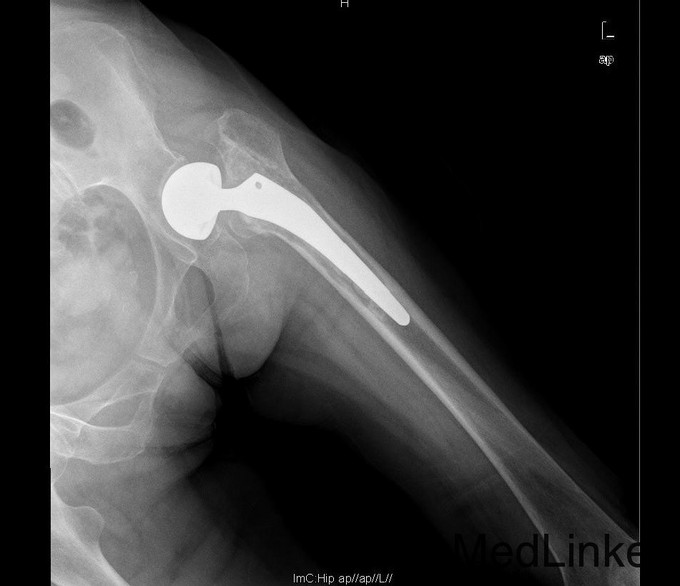

诊断:左双动股骨头置换术后假体松动、下沉、股骨骨缺损(PaproskyII型) 治疗:患者在全麻下左双动股骨头假体取出+同种异体骨植骨+左全髋关节翻修术,术后予以抗炎(二联)+抗凝+镇痛+护胃+补液等治疗,并予以抗骨质疏松药物

出院时左髋可屈曲90°,伸直0°,外展30° 讨论: 1、髋臼侧是否置换关键看什么? 2、Paprosky分型? 3、高龄患者行骨科大手术围手术期应着重注意哪些方面?( 体力、肺部感染、液体量与心功能、营养与饮食、锻炼与下肢深静脉血栓~~~~~) 4、假体柄的选择有何要求? 5、术后1天与术后3月的片子有何差别,试分析原因